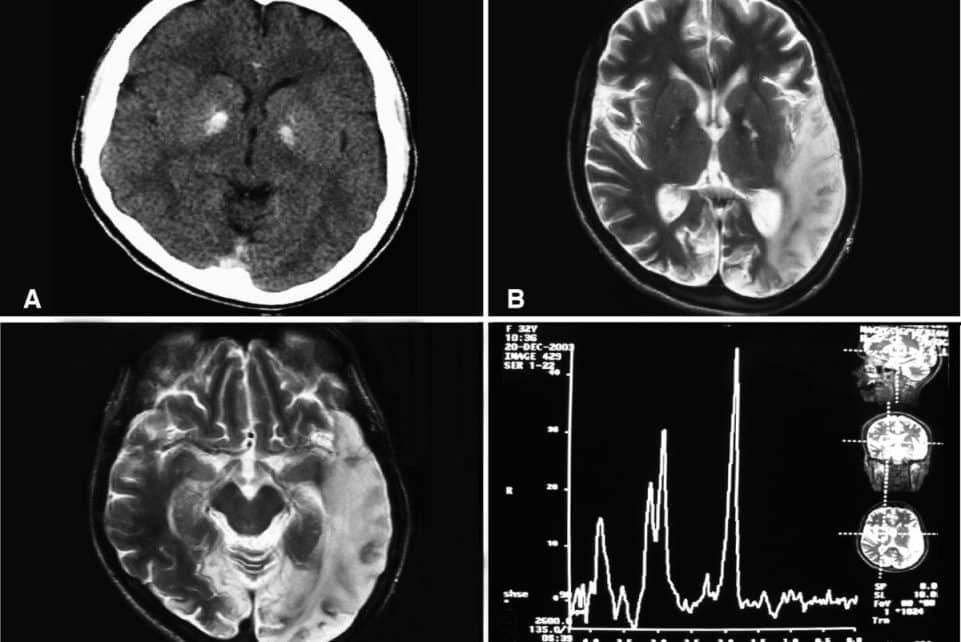

Tyrimo mastas – išskirtinis. Mokslininkai sujungė duomenis iš 3 737 kognityviškai sveikų dalyvių, stebėtų kelerius metus. Analizė apėmė 10 343 smegenų magnetinio rezonanso tomografijos (MRT) tyrimus ir 13 460 atminties įvertinimų, surinktų keliose ilgalaikėse stebėjimo studijose.

Tyrimo rezultatai atskleidė sudėtingą vaizdą. Kaip ir tikėtasi, ypatingą reikšmę turėjo hipokampas – smegenų sritis, atsakinga už atmintį ir mokymąsi. Tačiau paaiškėjo, kad atminties silpnėjimas nėra susijęs tik su vienos smegenų dalies pokyčiais.

Mažėjantis smegenų audinio tūris buvo susijęs su prastesne epizodine atmintimi, ir tai nestebino. Vis dėlto šis ryšys nebuvo vienodas visose dalyvių grupėse. Jis ryškėjo didėjant amžiui, ypač sulaukus daugiau nei 60 metų, ir buvo stipriausias tarp tų žmonių, kurių smegenų nykimas vyko sparčiau nei vidutiniškai.